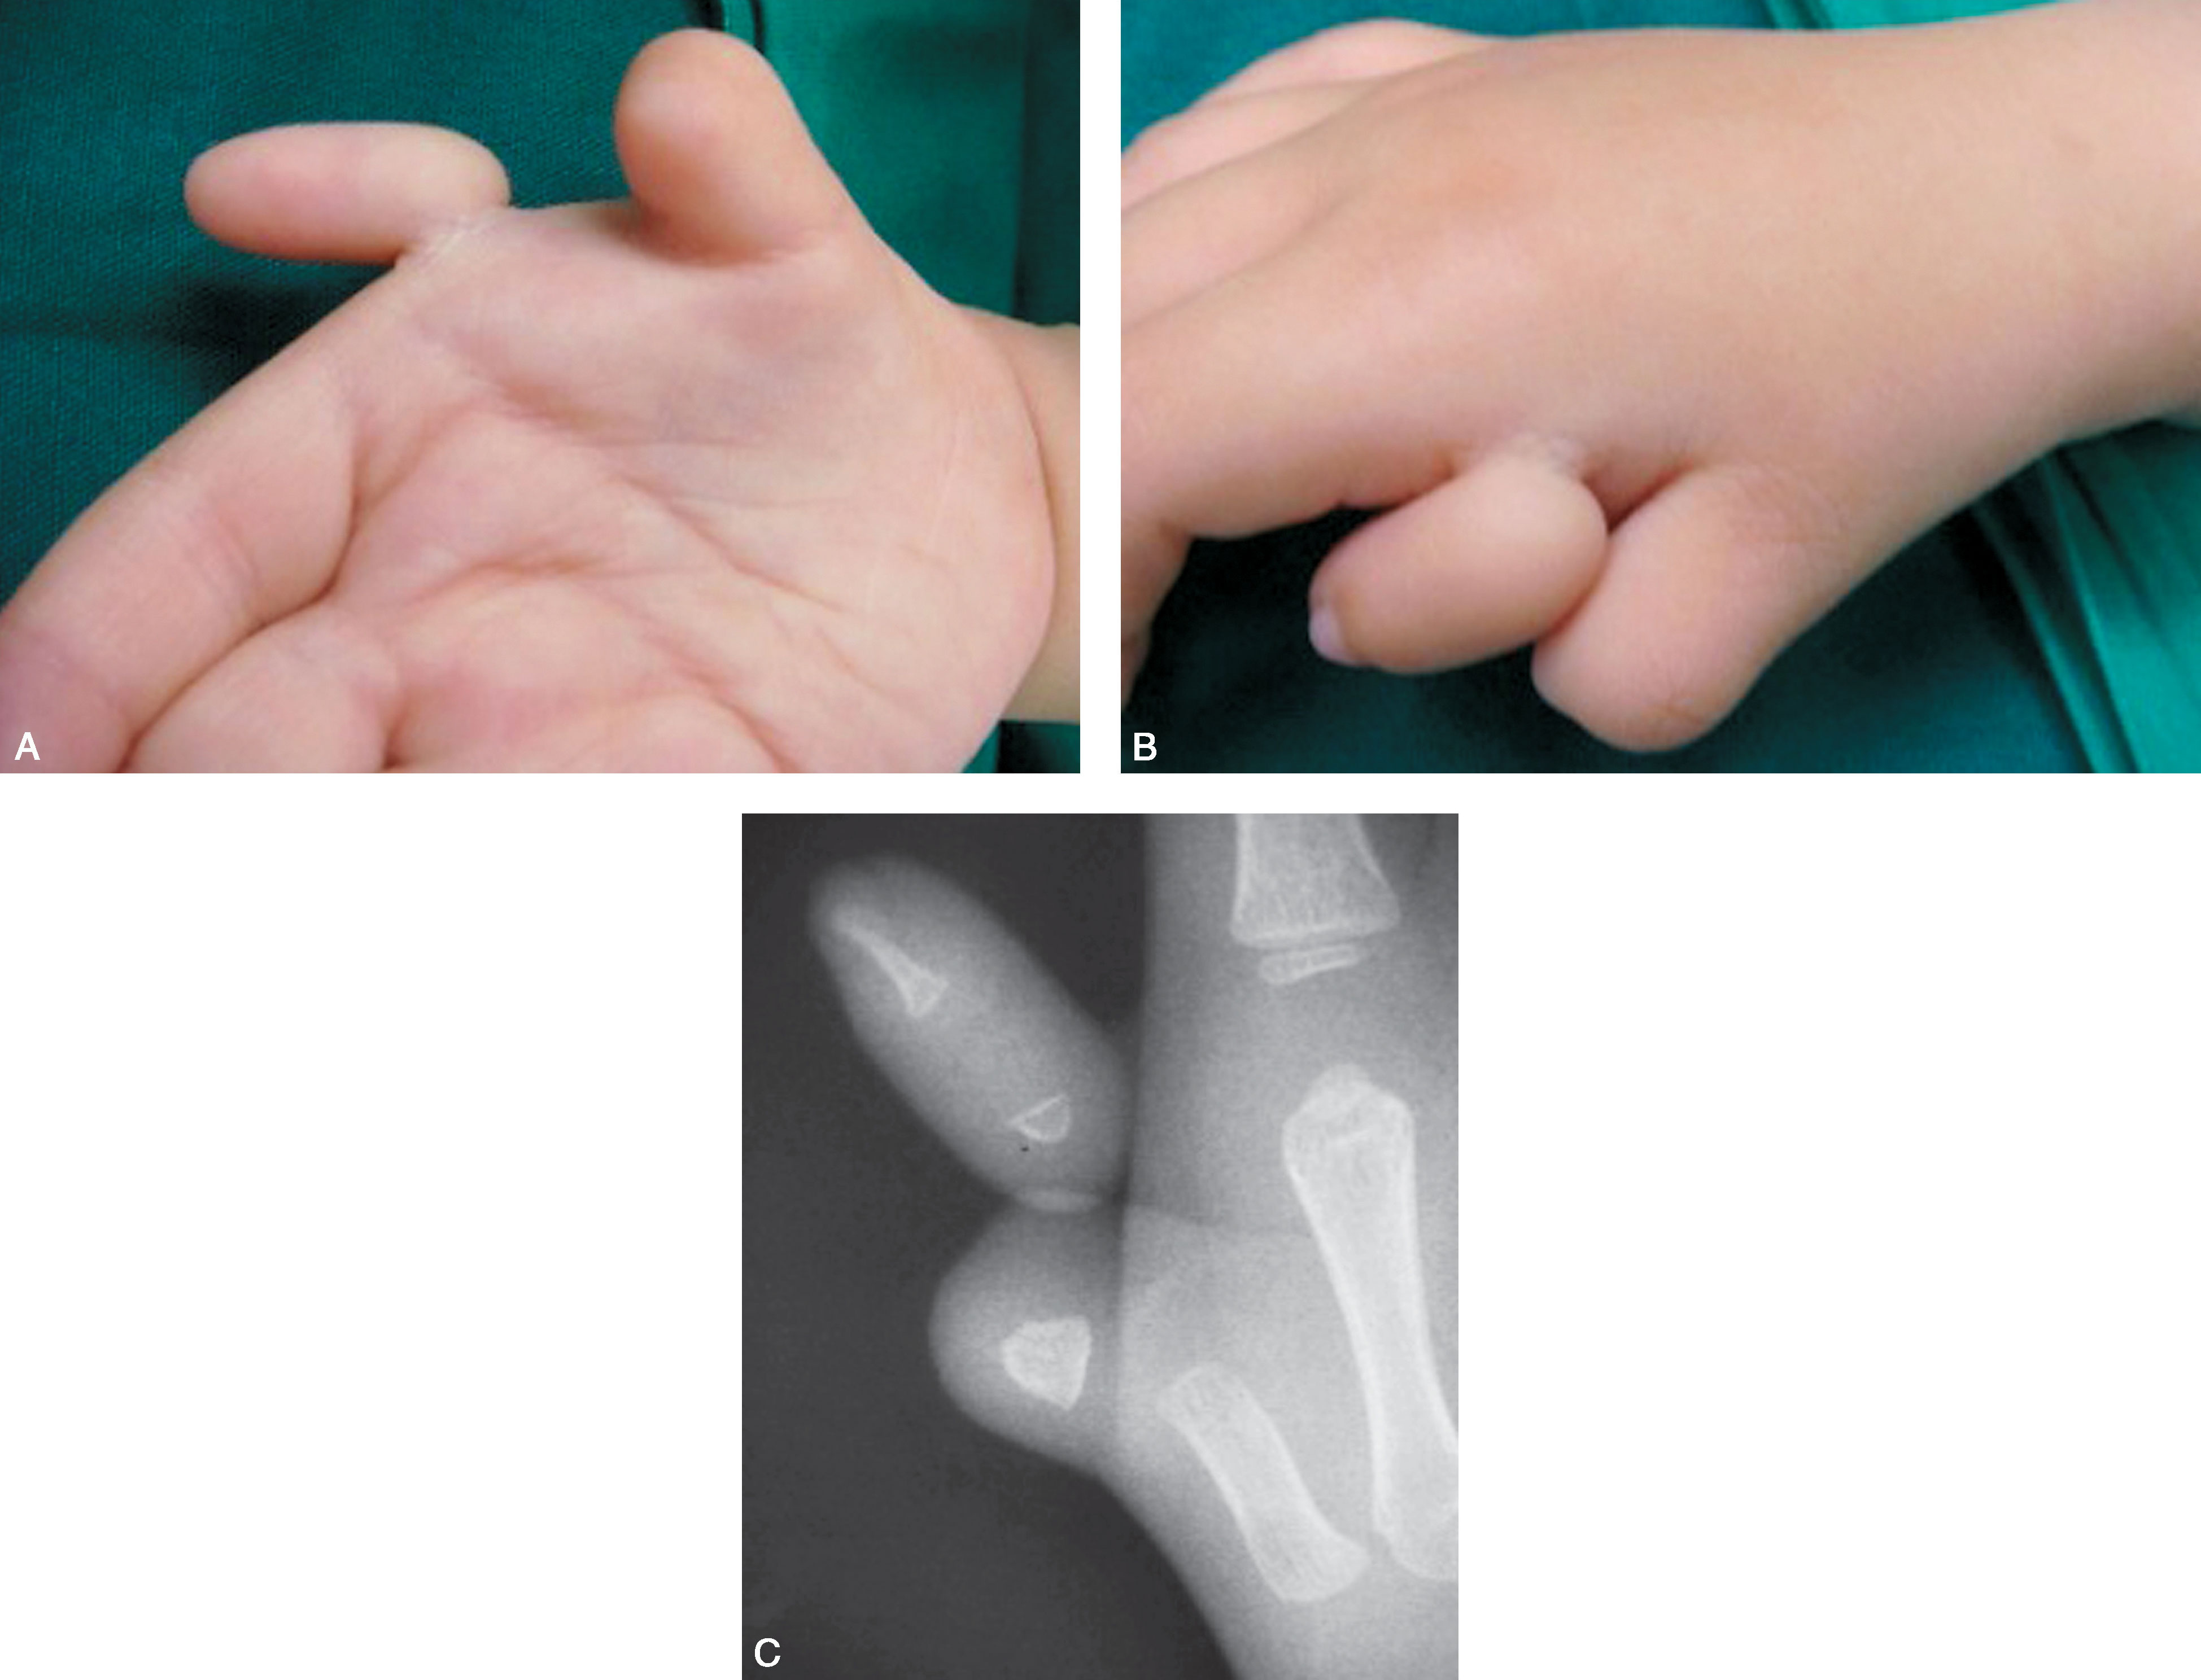

图2-1-65 三拇指畸形病例1

A.右手三拇指畸形,中央拇指发育较好;B.X 线片显示尺侧和桡侧拇指骨关节发育较差,中央拇指骨关节发育相对好,但为三节指骨,选择保留中间拇指,桡、尺侧拇指切除,术中需修复保留的中央拇指掌指关节两侧的关节囊韧带及拇内收肌止点,桡侧需重建拇短展肌止点,近侧指间关节复位固定,远侧指间关节融合